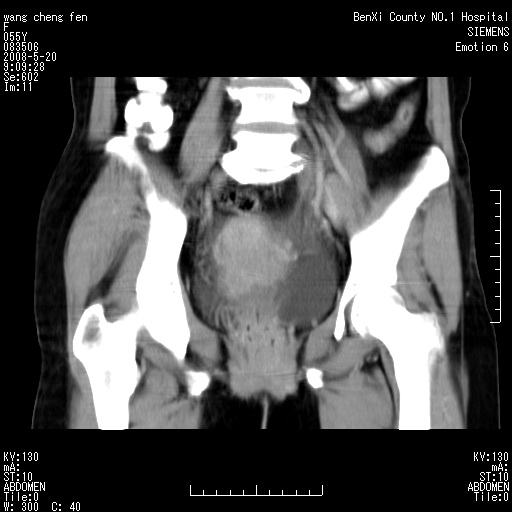

女、绝经后阴道流血3个月

左侧附件区巨大囊实性病灶,边缘光整,病灶囊壁较厚,增强示囊壁及实性部分明显强化,强化呈度与宫体实质大致相同,宫腔积液征像,未见盆腔积液等其他异常,考虑左侧卵巢囊腺癌,不除外囊腺瘤及浆膜下肌瘤坏死

左侧附件区巨大囊实性病灶,边缘光整,病灶囊壁较厚,增强示囊壁及实性部分明显强化,强化呈度与宫体实质大致相同,宫腔积液征像,未见盆腔积液等其他异常。绝经后阴道流血3个月,结合病史左侧卵巢囊腺癌首先考虑,宫腔扩大不除外累及。期待结果。

支持浆膜下子宫肌瘤.之前由于网络原因未看全图片,现在重看,宫颈见一类圆形低密度影,增强轻度强化,低于肌层强化,宫腔扩大,考虑宫颈癌伴宫腔积液可能性大.